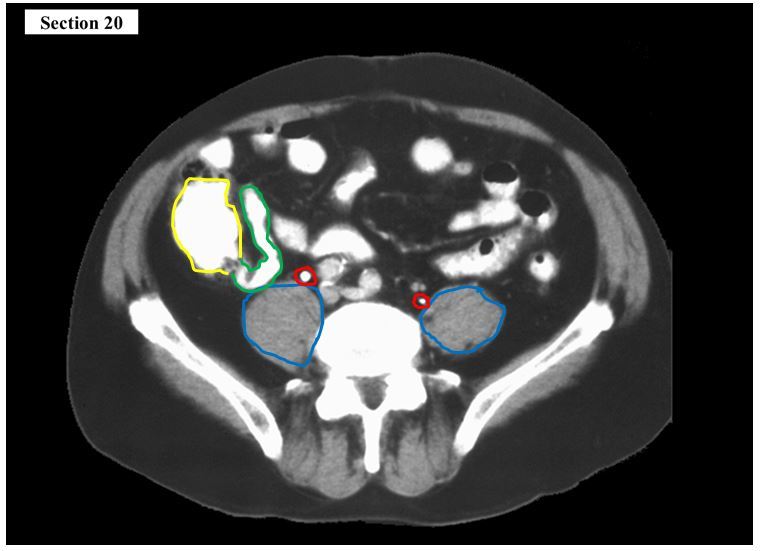

15

Q

The green structure is the ___ and it is attached to the yellow organ which is the ___

A

right ureter

urinary bladder